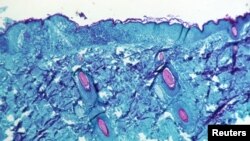

Una sección de tejido de la piel, extraída de una lesión en la piel de un mono que había sido infectado con el virus de la viruela del mono, se ve con un aumento de 50X en el cuarto día del desarrollo de la erupción en 1968. CDC/via REUTERS.